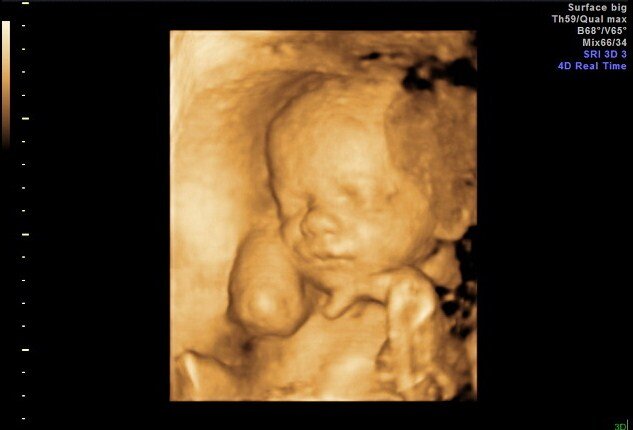

Центр медицины плода – признанный экспертный центр пренатальной диагностики с развитой сетью филиалов, в котором все исследования, в т.ч. и нейросонография проводятся с максимальной точностью и тщательностью врачами-экспертами международного уровня на передовом оборудовании, благодаря которому на экране монитора создаются 3D/4D-изображения не только самих структур головного мозга плода, но и его сосудов, что совсем недавно было невозможно.